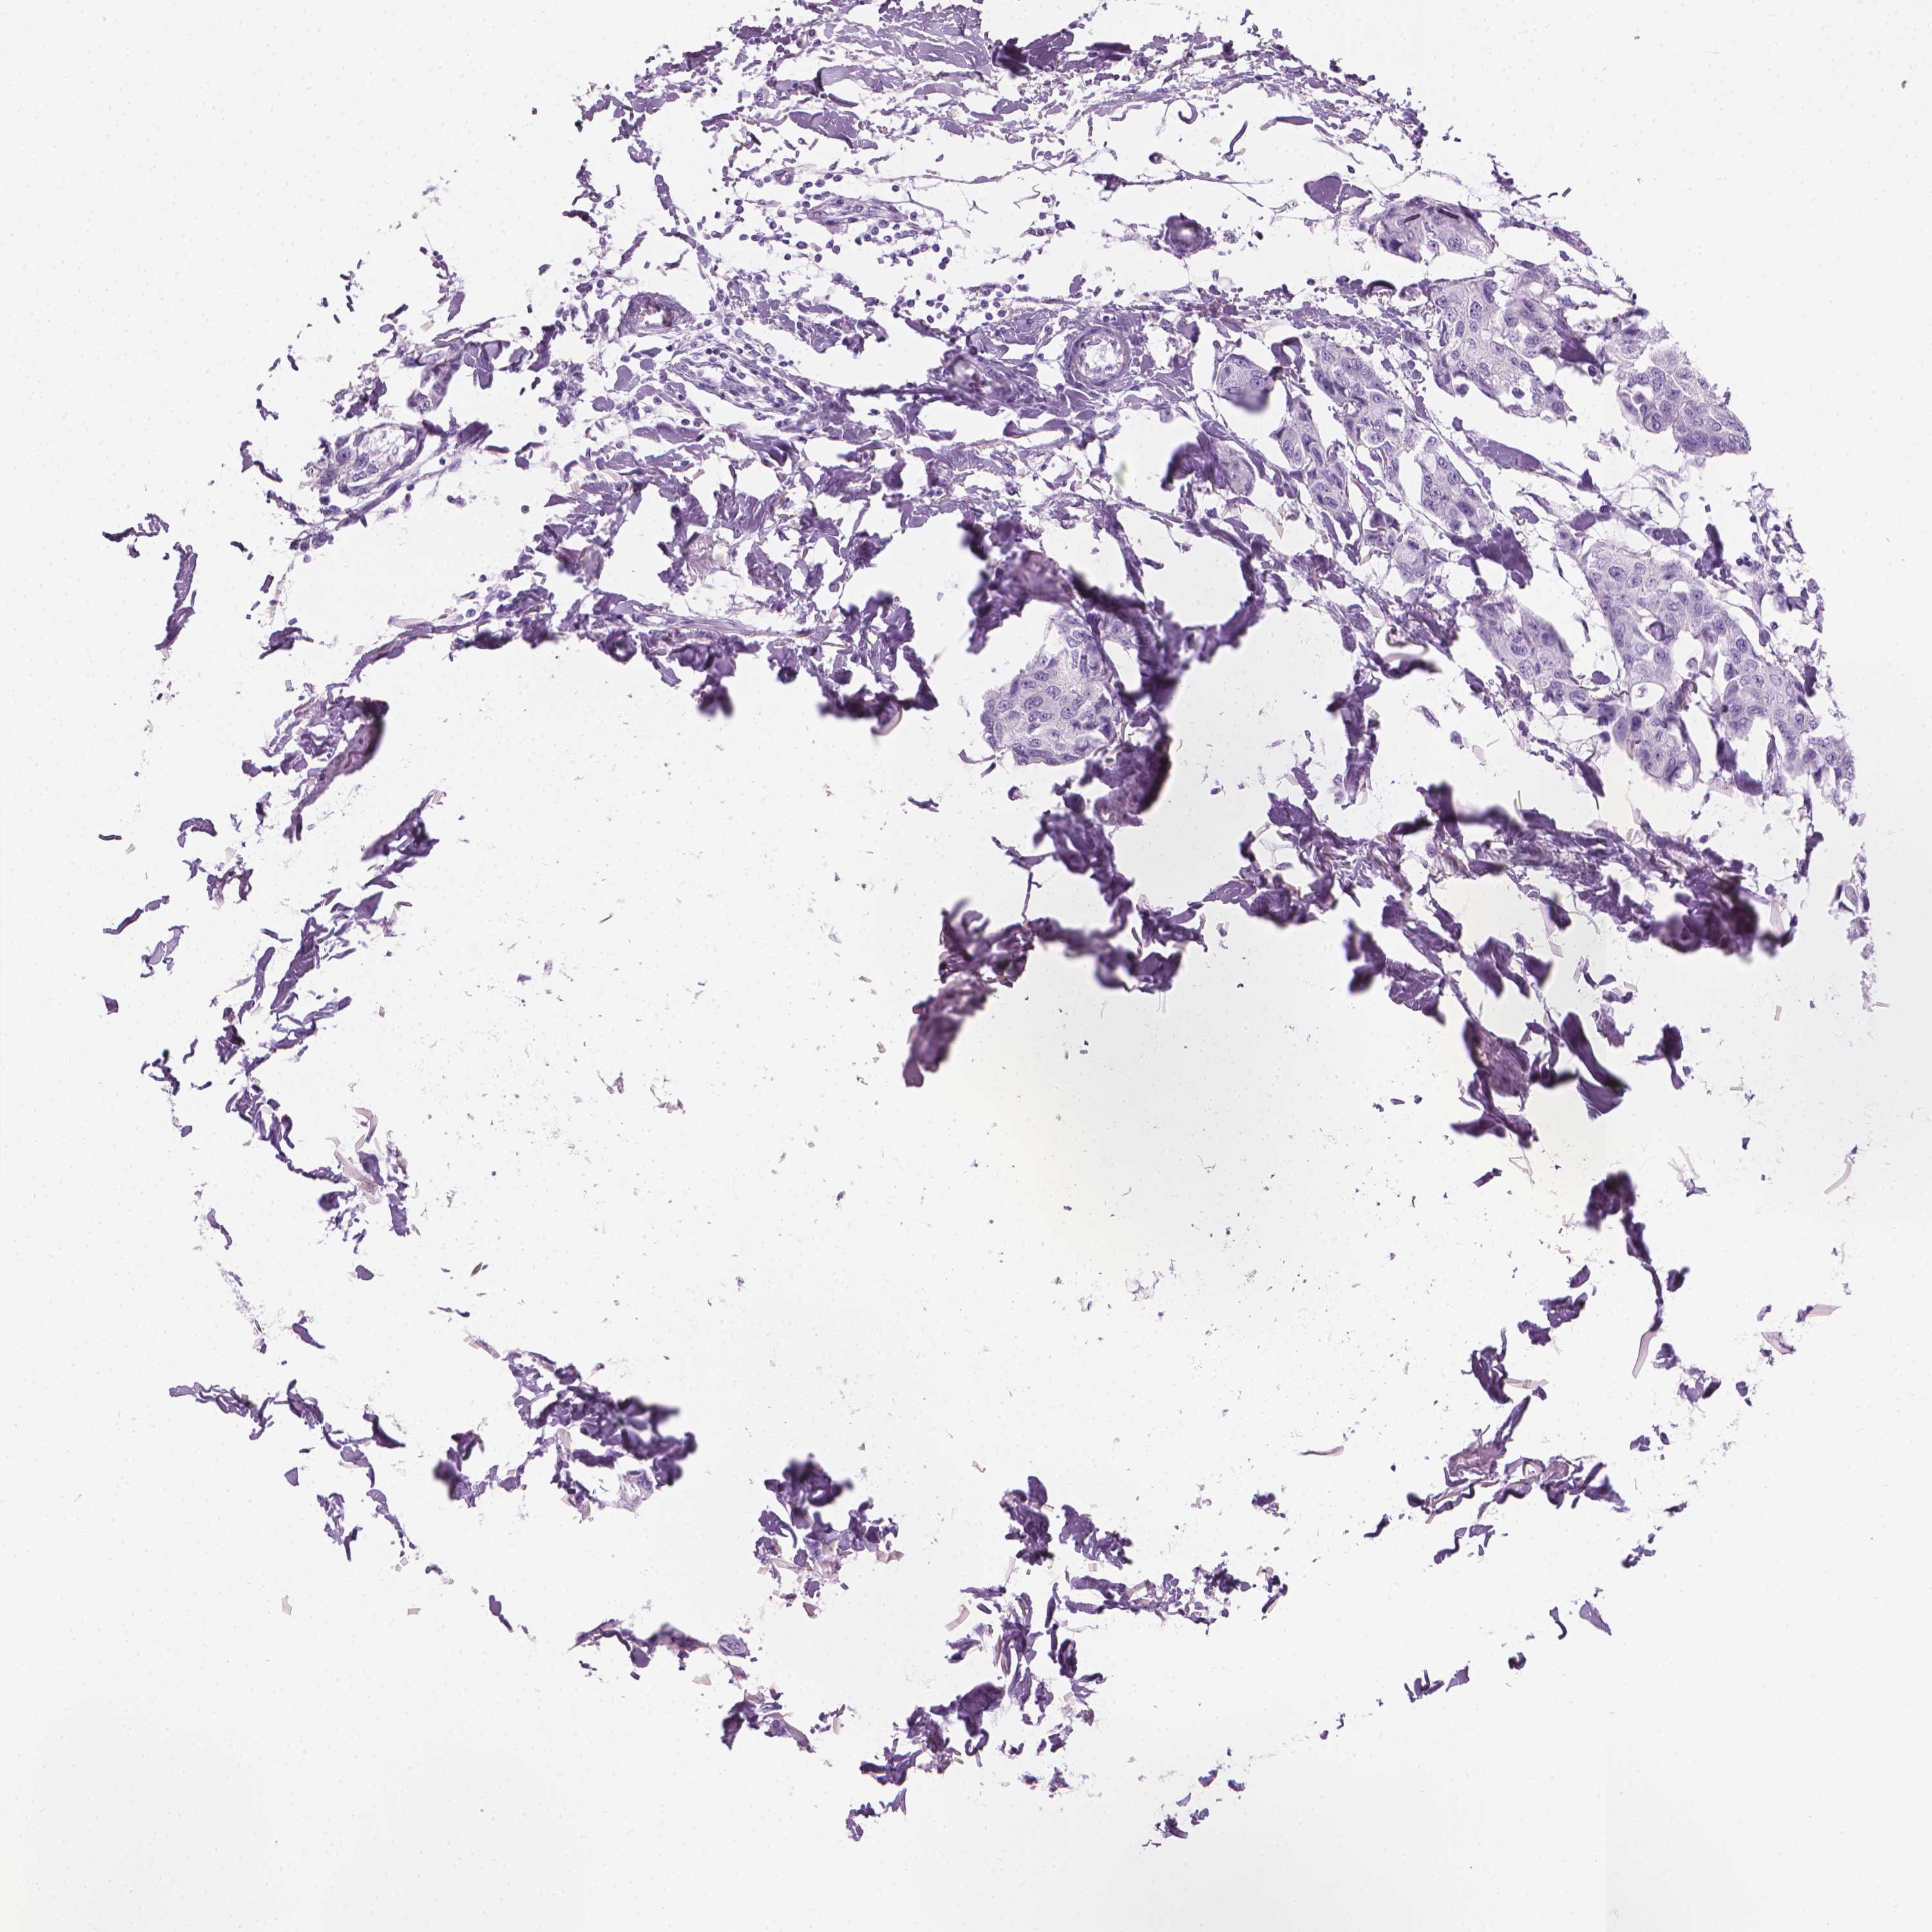

Breast cancer

Human cancer

Breast invasive carcinoma